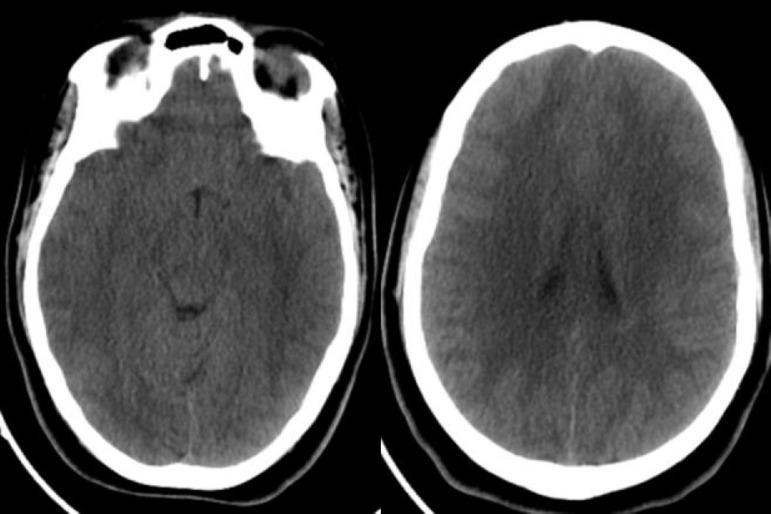

We described in this article a 19-year-old girl with an intracranial hypertension as an initial presentation of neuropsychiatric lupus. The brain MRI showed diffuse, bilateral and symmetrical white and grey matter hyperintensities. These lesions completely disappeared after 3 months of treatment. Diffuse cerebral edema with or without leukoencephalopathy in neuropsychiatric systemic lupus erythematosus is an extremely rare entity.

我们在本文中描述了一名19岁女孩,其以颅内高压作为神经精神性狼疮的初始表现。脑部磁共振成像显示弥漫性、双侧对称的白质和灰质高信号。经过3个月的治疗,这些病变完全消失。神经精神性系统性红斑狼疮中伴有或不伴有白质脑病的弥漫性脑水肿是一种极其罕见的情况。